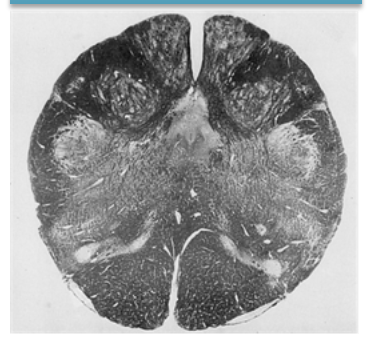

What level of brain stem is this?

What level of brainstem is this, specifically?

What does the caudal pons (at CN VI) cross section kind of resemble?